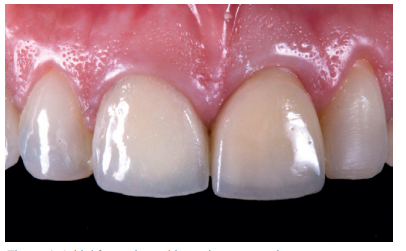

This describes the clinical case of a 52-year-old woman who came to the dentist surgery due to de-cementation of a tooth-supported metal-ceramic crown on tooth 2.1 (ICSI), see Figures 1-3. The patient reported it as of high concern for her aesthetically.

After the 6-month review, excellent stability of all periimplant tissues was verified, with correct volume at the vestibular level, as well as the maintenance of optimal aesthetics and functionality (Figure 30).